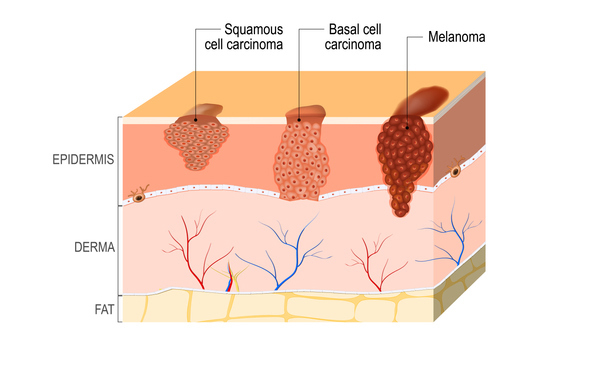

Squamous Cell Carcinoma Skin Cancer Symptoms Causes Treatment

What is Squamous Cell Carcinoma top, Squamous Cell Carcinoma SCC Symptoms Stages Risk Factors and top, Squamous cell carcinoma of the skin Symptoms and causes Mayo top, Squamous Cell Carcinoma Symptoms Causes Treatment More top, What Are Basal and Squamous Cell Skin Cancers Types of Skin top, Squamous cell carcinoma SCC symptoms diagnosis and treatment top, Squamous cell carcinoma Wikipedia top, Squamous cell carcinoma what is it symptoms and treatment Top top, What is Squamous Cell Carcinoma Oakland Hills Dermatology top, Squamous Cell Carcinoma OSUCCC James top, Squamous cell carcinoma SCC Juniper Dermatology top, Squamous Cell Carcinoma SCC Guidelines Diagnose Treat top, Squamous Cell Carcinoma Overview Moffitt top, Squamous Cell The Definitive Guide Biology Dictionary top, Skin cancer types Squamous cell carcinoma causes top, Skin Cancer Types and Their Features top, Squamous Cell Carcinoma Skin Cancer Symptoms Causes Treatment top, Squamous Cell Carcinoma Treatment Birmingham Alabaster AL top, Squamous Cell Carcinoma Pictures Symptoms and More top, Squamous cell skin cancer Information Mount Sinai New York top, Squamous cell carcinoma Wikipedia top, Squamous cell carcinomas 8 things to know about the cancer of top, Squamous Cell Carcinoma Pennsylvania Dermatology Specialists top, Squamous Cell Carcinoma in the Lungs What to Know top, Squamous Cell Carcinoma Pictures Symptoms and More top, Squamous Cell Carcinoma Facts City of Hope top, What You Should Know About Squamous Cell Carcinoma top, Squamous Cell Carcinoma Skin Disorder Guide TODAY top, Squamous Cell Carcinoma Risks and Diagnosis top, Types of skin cancer Squamous cell and basal cell carcinoma top, Squamous Cell Carcinoma What You Need to Know top, Squamous Cell Carcinoma Squamous Cell Skin Cancer Rochester top, What Are the Different Types of Skin Cancer top, Squamous Cell Carcinoma Treasure Valley Dermatology Dr. Dustin top, Squamous Cell Carcinoma Dermatology of Seattle Bellevue top.

What is Squamous Cell Carcinoma top, Squamous Cell Carcinoma SCC Symptoms Stages Risk Factors and top, Squamous cell carcinoma of the skin Symptoms and causes Mayo top, Squamous Cell Carcinoma Symptoms Causes Treatment More top, What Are Basal and Squamous Cell Skin Cancers Types of Skin top, Squamous cell carcinoma SCC symptoms diagnosis and treatment top, Squamous cell carcinoma Wikipedia top, Squamous cell carcinoma what is it symptoms and treatment Top top, What is Squamous Cell Carcinoma Oakland Hills Dermatology top, Squamous Cell Carcinoma OSUCCC James top, Squamous cell carcinoma SCC Juniper Dermatology top, Squamous Cell Carcinoma SCC Guidelines Diagnose Treat top, Squamous Cell Carcinoma Overview Moffitt top, Squamous Cell The Definitive Guide Biology Dictionary top, Skin cancer types Squamous cell carcinoma causes top, Skin Cancer Types and Their Features top, Squamous Cell Carcinoma Skin Cancer Symptoms Causes Treatment top, Squamous Cell Carcinoma Treatment Birmingham Alabaster AL top, Squamous Cell Carcinoma Pictures Symptoms and More top, Squamous cell skin cancer Information Mount Sinai New York top, Squamous cell carcinoma Wikipedia top, Squamous cell carcinomas 8 things to know about the cancer of top, Squamous Cell Carcinoma Pennsylvania Dermatology Specialists top, Squamous Cell Carcinoma in the Lungs What to Know top, Squamous Cell Carcinoma Pictures Symptoms and More top, Squamous Cell Carcinoma Facts City of Hope top, What You Should Know About Squamous Cell Carcinoma top, Squamous Cell Carcinoma Skin Disorder Guide TODAY top, Squamous Cell Carcinoma Risks and Diagnosis top, Types of skin cancer Squamous cell and basal cell carcinoma top, Squamous Cell Carcinoma What You Need to Know top, Squamous Cell Carcinoma Squamous Cell Skin Cancer Rochester top, What Are the Different Types of Skin Cancer top, Squamous Cell Carcinoma Treasure Valley Dermatology Dr. Dustin top, Squamous Cell Carcinoma Dermatology of Seattle Bellevue top.